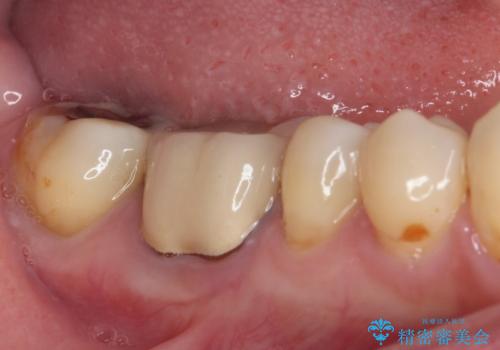

- 下顎の奥歯に頻繁に物が挟まるとのことで来院された患者様です。

最近ものが挟まりやすくなったり、冷たいものがしみるようになったりといった症状があり、診査したところ、歯質の欠損や不適修復物などが認められました。

精度の高いセラミックインレーによる修復治療を行うこととしました。